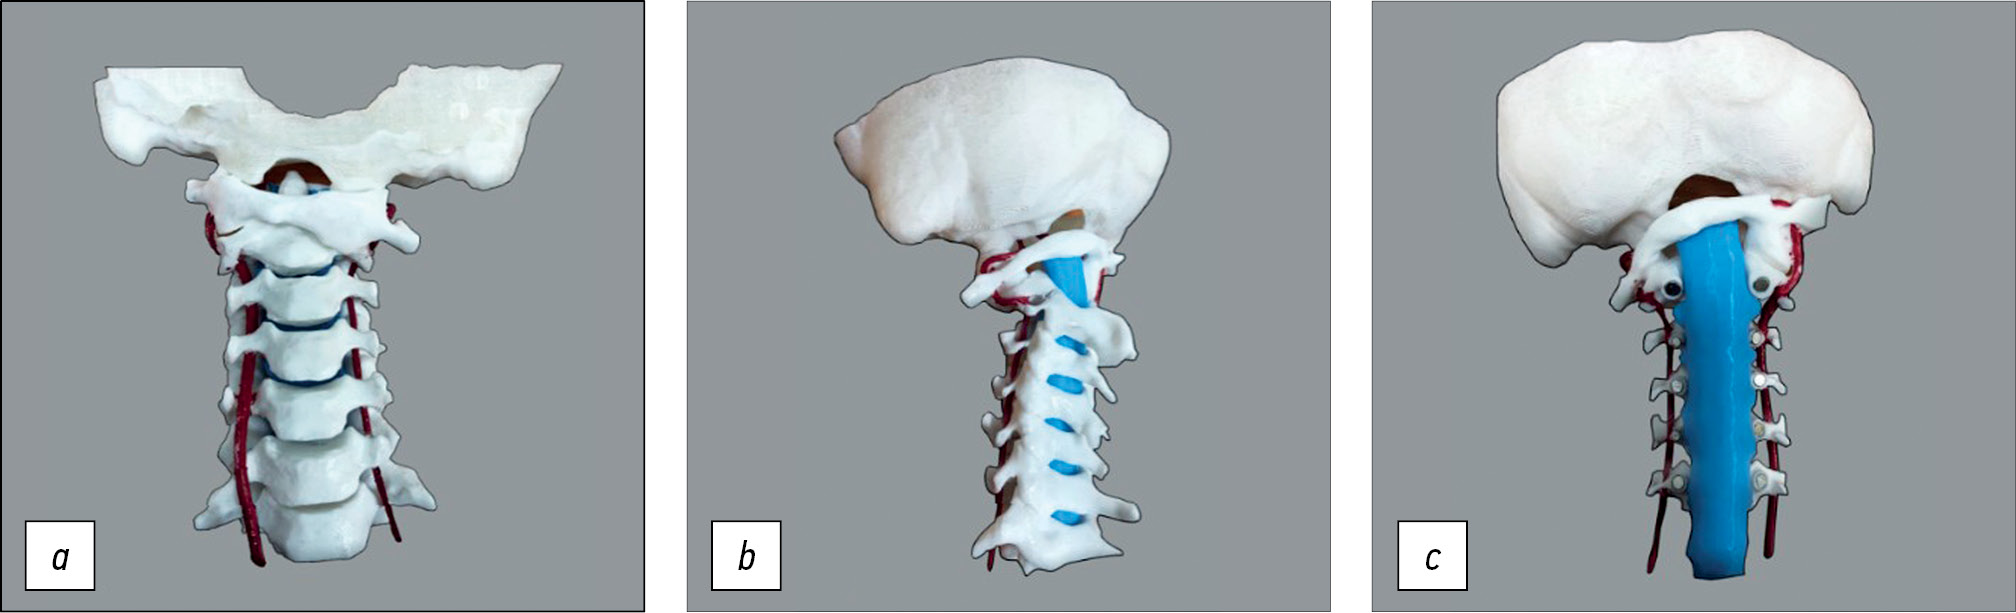

Given the gross atlantoaxial dislocation with spinal canal stenosis, spinal cord compression, and bone block formation in the left lateral atlantoaxial joint, correction of C1 subluxation under intraoperative halo-traction with the release of the left lateral atlantoaxial joint was decided. To improve the quality of preoperative planning and reduce the risks of a. vertebralis injury during the release of the lateral atlantoaxial joint, the patient underwent CT and myelo- and angiography of the cervical spine (Fig. 4). A customized 3D model of the craniovertebral region was made, showing the vertebral arteries and spinal cord based on CT myelography and CT angiography (Fig. 5).

Fig. 5. 3D model of the patient’s cervical spine with visualization of the a. vertebralis and spinal cord: a — anterior view, b — lateral view, c — posterior view with the cervical vertebral arches removed.